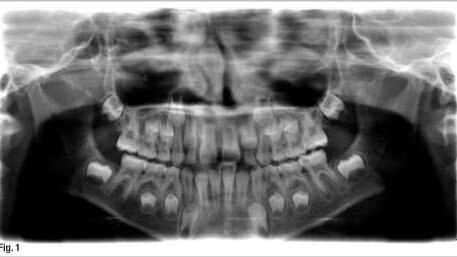

Une jeune patiente a été adressée au cabinet, souffrant d'une molaire inférieure. La radio a indiqué une lésion sur les deux racines, avec les canaux mésiaux non encore pleinement formés, en ce qui concerne la longueur et le diamètre (fig. 1).

Après discussion du cas avec les parents et l'explication de la nouvelle technique, j'ai ouvert la molaire en conditions très aseptiques. La racine distale a montré des signes de léger saignement, donc la pulpe était relativement vitale. Les racines mésiales n'ont pas montré de signes de saignement, mais la pulpe résiduelle était clairement visible au microscope. Après irrigation copieuse à la chlorhexidine dans les racines mésiales et distales, une solution de SmearClear (SybronEndo) a été instillée et une activation passive avec un lime K N° 10 a été exécutée dans les canaux mésiaux, avec juste un peu de saignement. L'eau distillée a été employée pour rincer tous les produits chimiques et une pâte antibiotique duelle a été placée. Ensuite, un ionomère de verre a été placé en technique sandwich, sous un composite. (fig. 2). La patiente ne s'est plainte d'aucune douleur, juste un léger inconfort.